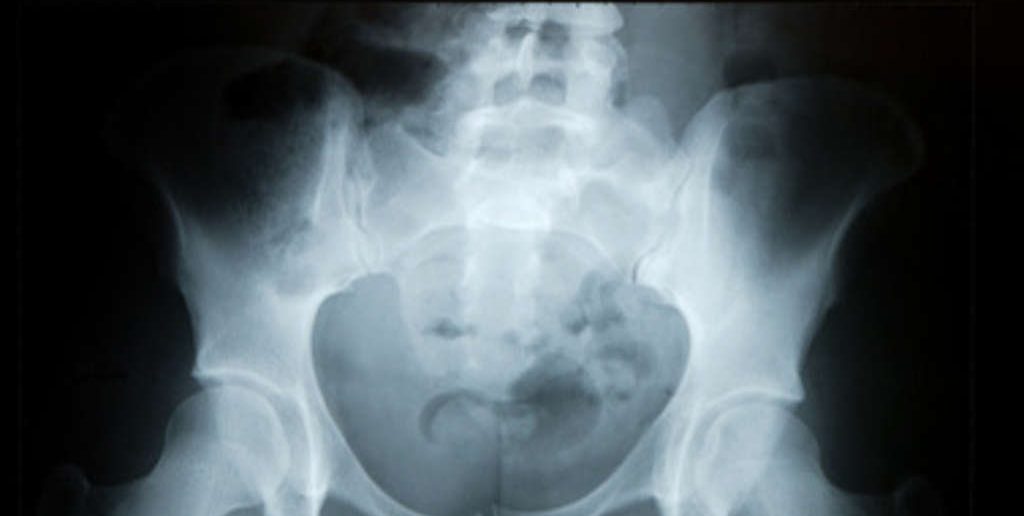

Zur Diagnose des Leistenbruches zählen zunächst das Abtasten der schmerzenden Leistenregion, sowie eine Funktionsprüfung der Hüfte, der Symphyse, des Kreuzbein- Darmnbein- Gelenk und der Muskulatur. Mit dem Ultraschallgerät kann eine Entzündung diagnostizert werden und festgestellt werden, ob es sich um eine ältere oder aktuelle Verletzung handelt. Im MRT wird untersucht, ob es sich um Sehnen- Muskel- oder Knochenveränderungen handelt. Das Röntgen dient zum Ausschluss von arthrtischen Veränderungen im Bereich der Hüfte, der Symphyse oder des Kreuzbein.